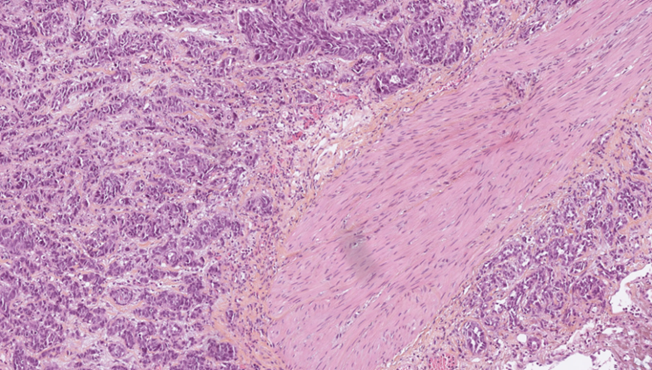

Des équipes du monde entier seront mises en concurrence pour développer le modèle d’intelligence artificielle (IA) le plus performant capable de prédire l’efficacité de l’immunothérapie chez les patients atteints d’un carcinome urothélial de la vessie. La compétition se basera sur l’analyse d’une base de données inédite d’environ 500 lames histologiques numérisées.

Une base de données unique de lames histologiques

Trois centres français participent à la constitution et l’annotation d’une base de données inédite d’environ 500 lames histologiques numérisées de carcinome urothélial de la vessie.